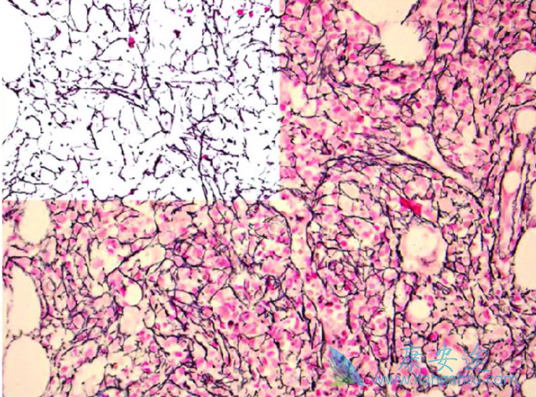

2019年8月16日,FDA批准Inrebic (fedratinib)胶囊用于中危-2或高危骨髓纤维化成人患者。骨髓纤维化是一种罕见的骨髓疾病,患者可能出现以下症状:极度疲乏、气短、肋下疼痛、发热、盗汗、瘙痒和骨痛。在此之前,只有Jakafi(鲁索替尼)于2011年获批用于骨髓纤维化患者。